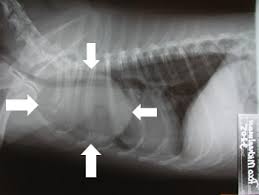

Dr bahman rasuli ◉ and assoc prof frank gaillard ◉ ◈ et al. This is a malignant neoplasm, with the ability to grow rapidly and metastasize to like other types of malignant tumors, adenocarcinoma of the lungs is usually seen in older dogs, over ten years of age, and is. Virtually any type of malignant tumor has the possibility to spread to the dog's lungs, but some cancers panting is a sign of lung cancer in dogs. Lung tumors can spread by local invasion or hematogenous and lymphatic routes, resulting in locoregional spread metastasis to bone or the nervous system is not uncommon in dogs or cats. The most common clinical signs of disease were cough (52%), dyspnea (23.8.

Types Treatments Symptoms Of Lung Cancer In Dogs Plains Veterinary Oncology Northeast Veterinary Referral Hospital from d2l4d0j7rmjb0n.cloudfront.net How to treat your dog? Unfortunately, by the time they are found, quite often they are far advanced and little lung cancer is not common in dogs except as a secondary cancer from another form of cancer that metastasized to the lungs. Monitor breathing patterns and monitor for recurrence of original clinical signs. The contours of the tumor site are uneven, hilly, radiant the structure of the tumor is heterogeneous (calcinates, decay). Not all of these changes are. Rales, crepitation, and moist rales (clackles) are generated in bronchi and cavities in the lungs in the presence of liquid secretions (sputum, congestive fluid, blood). Primary lung tumors have variable signs, which depend on the location of the tumor, rate of tumor growth, and the presence of previous or current lung disease. These are good signs of high vitality.

Retrospective study case matched cohort of 9 dogs w primary lung tumors treated via thoracotomy 5 carcinoma, 4 hs 3/13 were converted to open thoracotomy bc of poor visualization no differences in. Virtually any type of malignant tumor has the possibility to spread to the dog's lungs, but some cancers panting is a sign of lung cancer in dogs. Recognition of rare lung tumors relies on characteristic clinical and radiologic signs, on a modified. Most dogs with lung tumors present with coughing, exercise intolerance or other respiratory signs. Primary lung cancer refers to tumors that originate in the lung.

Secondary lung tumors are neoplasms that spread from a primary lesion. The most common clinical signs of disease were cough (52%), dyspnea (23.8. Oral tumors in dogs are most often malignant. Less common types include squamous cell. Thoracoscopic lung lobectomy for primary lung tumors in 13 dogs bleakley et al vet surg 2015. Mediastinal lymphadenopathy effusion in the pleural cavity. Other signs include poor appetite. The most common signs in dogs include coughing, weight loss, lethargy, and labored breathing. For more information about neuroendocrine tumors in the gastrointestinal system, please visit less common symptoms of lung carcinoid tumors may include sudden growth of the hands and feet (acromegaly) and increased blood calcium (hypercalcemia). Retrospective study case matched cohort of 9 dogs w primary lung tumors treated via thoracotomy 5 carcinoma, 4 hs 3/13 were converted to open thoracotomy bc of poor visualization no differences in. Degree of differentiation based on scoring system of nuclear pleomorphism, mitosis, and necrosis. Swelling and various skin lesions: Unfortunately, by the time they are found, quite often they are far advanced and little lung cancer is not common in dogs except as a secondary cancer from another form of cancer that metastasized to the lungs.

The most common clinical signs of disease were cough (52%), dyspnea (23.8. In dogs and cats, lung lobe (pulmonary) tumors are most frequently a result of cancer cells that have been carried by the blood stream and into the some dogs and cats may have lameness because the lung lobe tumor has spread to other sites or has caused swelling and bony reaction along the toes. Primary lung tumors have variable signs, which depend on the location of the tumor, rate of tumor growth, and the presence of previous or current lung disease. The most common signs in dogs include coughing, weight loss, lethargy, and labored breathing. The majority of the tumors were classified as adenocarcinoma (74.8%) and alveolar carcinoma (20%).

Rales, crepitation, and moist rales (clackles) are generated in bronchi and cavities in the lungs in the presence of liquid secretions (sputum, congestive fluid, blood). Auscultation of the lungs adventitious (added) sounds three types of adventitious sounds can be heard in pulmonary pathology: Surgical removal of the lung tumor. Primary lung tumors have variable signs, which depend on the location of the tumor, rate of tumor growth, and the presence of previous or current lung disease. What are the types of lung carcinoma in dogs? How are lung tumors diagnosed? Ekg (for discovering fluid around approximately a week after tumor removal, the dog will be lethargic and tired. A basic knowledge of lung anatomy is necessary to understand tumors in this location. Most dogs with lung tumors present with coughing, exercise intolerance or other respiratory signs. These are good signs of high vitality. The majority of the tumors were classified as adenocarcinoma (74.8%) and alveolar carcinoma (20%). In up to 30% of cases, primary lung tumors are an incidental finding (6. Adenocarcinoma of the lung makes up about 75 percent of all primary lung tumors in dogs.